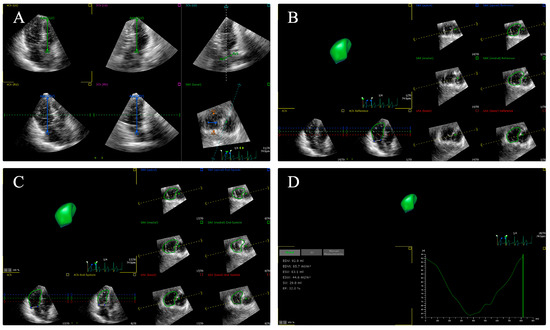

3. Two-Dimensional Echocardiography and Tissue Doppler Imaging

4.3. Two-Dimensional Speckle Tracking Echocardiography

4.4. Three-Dimensional Speckle Tracking Echocardiography